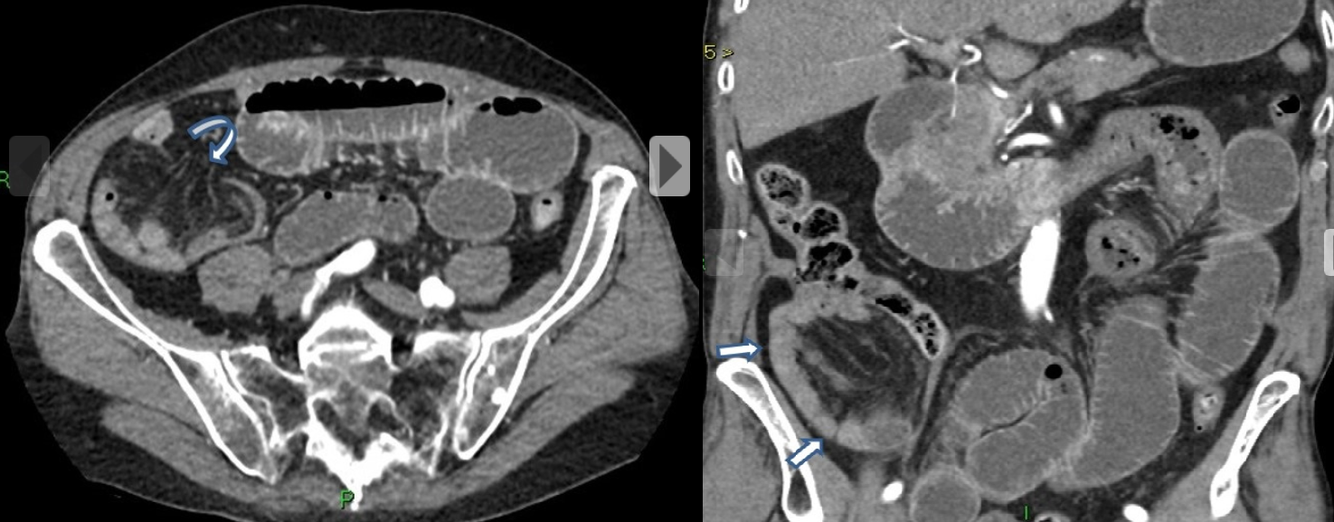

Homem, 45 anos, Dor abdominal, distensão e parada da eliminação de fezes e flatos.

Hérnia interna - pericecal.

Causa de obstrução intestinal de delgado.

Segundo tipo mais comum de hérnia interna, perdendo para a paraduodenal.

A alça herniada geralmente consiste em um segmento ileal que se projeta através de um defeito no mesentério cecal (que pode ser congênito ou adquirido)